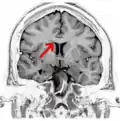

Coronal T2 (grey scale inverted) MRI of the brain at the level of the caudate nuclei emphasizing corpus callosum -